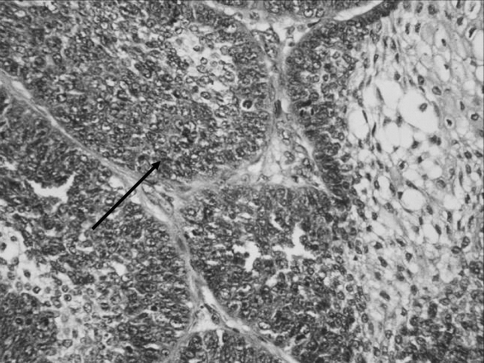

The surgical specimen consisted of multiple bits of soft tissue with the largest sample measuring 4 × 2 × 1 cm. The tissue was soft to firm with the external surface showing areas of congestion and papillary excrescences. The cut surface showed a nodular growth which was pearly white in colour with areas of congestion. Microscopic findings showed nests and islands of epithelium within a collagenous stroma. The cell nests were composed of a peripheral layer of polarised cells enclosing stellate to basaloid cells (Fig. 3). The cells showed large nuclei some of which showed prominent nucleoli and nuclear pleomorphism. Mitotic activity was seen with 3–4 mitotic figures/10 HPF. Central foci of necrosis were present (Fig. 4). No perineural or vascular invasion was seen. Impression was of a very aggressive type of ameloblastoma suggestive of ameloblastic carcinoma.

Fig. 3.

Tumour exhibiting the morphology of an ameloblastoma with high mitotic activity (arrow) and nuclear pleomorphism and basaloid hyperplasia (H&E ×400)